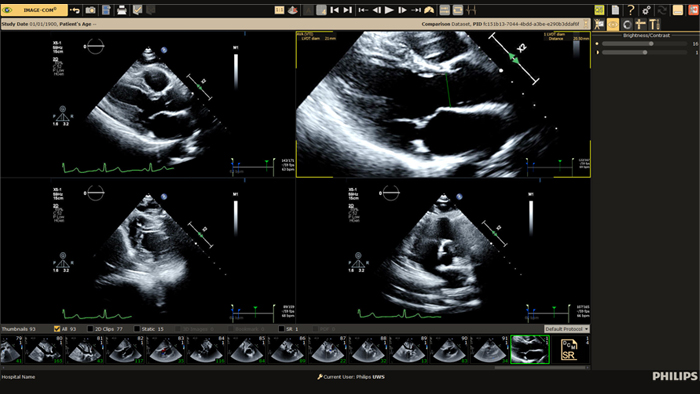

Philips Ultrasound Workspace

Allow for efficiency in viewing, analysis and reporting by giving care teams the flexibility to adopt different workflows based on their current and future needs.

Cardiovascular Workspace*

Provide a single point of access to a patient’s cardiovascular diagnostic information and multi-modality images, including prior exams, as well as findings, measurements and reports.